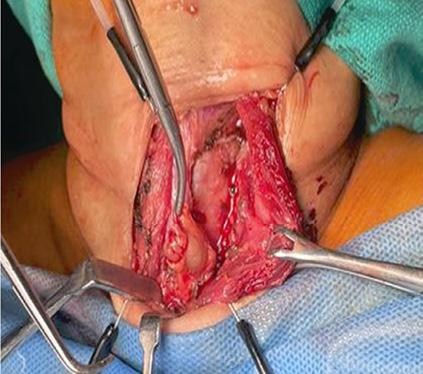

The patient had suffered trivial trauma to hip when she fell down in bathroom 3 months prior to presentation and she has been wheelchair bound since then. She was initially evaluated at a private hospital and was diagnosed as a case of pathological fracture of neck of left femur. Initial X-Ray skull, pelvis and LS spine revealed salt and pepper appearance, osteopenia with osteophytes and decreased L3‒L4 & L4‒L5 disc spaces (Figures 1A, 1B).

A. Salt pepper appearance of skull |

B. Multiple osteolytic lesion in skeletal bones, pelvis and LS spine |

Figure 1. |